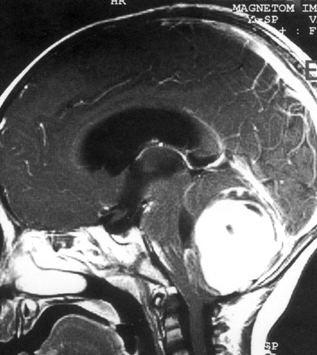

病历摘要:??患儿男性,11岁。半年前开始出现行走不稳,常无故跌倒。半月前出现发作性剧烈头痛,伴恶心呕吐。体检:T36℃,P100次/分,R22次/分,B...

问题 病历摘要:??患儿男性,11岁。半年前开始出现行走不稳,常无故跌倒。半月前出现发作性剧烈头痛,伴恶心呕吐。体检:T36℃,P100次/分,R22次/分,BP100/60mmHg,神清,言语较缓慢,双眼外展约不及边,双眼侧视时有小幅度水平眼震。四肢肌力正常,右上肢肌张力较低,坐位姿势不稳,常不自主摇晃,双上肢指鼻不准,行走蹒跚步态,足距扩大,身前倾。 下一步应首先行何种后续治疗?提示:经腰穿置管脑脊液外引流等处理,脑脊液渗漏停止。肿瘤病理为髓母细胞瘤。